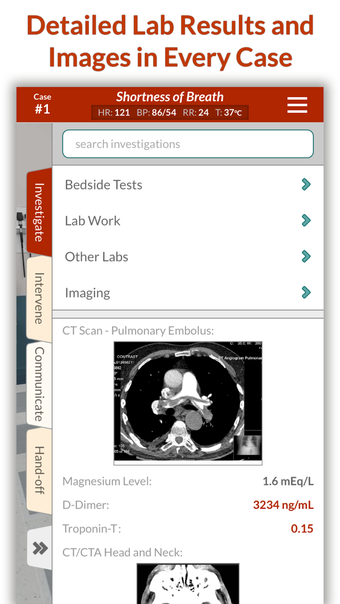

Full Code - Emergency Medicine Simulation è un'applicazione Android sviluppata da Minerva Medical Simulation Inc. È una versione completa con licenza di un'applicazione di stile di vita che rientra nella sottocategoria medica. È un'applicazione di simulazione intuitiva, mobile-first che offre oltre 160 casi virtuali realistici e un'interfaccia coinvolgente simile a un gioco, preferita dai professionisti medici di tutto il mondo. L'applicazione è progettata per aiutare gli studenti e i professionisti medici a acquisire fiducia nel trattamento di casi complessi e offre 0,5 crediti AMA PRA Categoria 1™ per ogni caso Full Code giocato con Full Code Pro+CME.

L'applicazione consente agli utenti di esercitarsi in diagnosi cliniche rare e rischiose in un ambiente sicuro in modo da poter affrontare casi complessi del mondo reale con fiducia. Con oltre 160 casi in 31 specialità, Full Code consente di esercitarsi in simulazioni mediche on-demand ogni volta che si ha una pausa, ovunque ci si trovi. L'applicazione è ottimizzata per la portabilità e l'accessibilità ed è disponibile su qualsiasi dispositivo mobile, desktop o tablet. Full Code è accreditato attraverso l'ACCME e, con la sua sottoscrizione PRO+CME, gli utenti possono completare i loro requisiti di formazione medica continua (CME) con sfide di simulazione flessibili e piacevoli. È un'applicazione eccellente per i professionisti medici che vogliono migliorare le proprie competenze e acquisire fiducia nel gestire casi complessi.